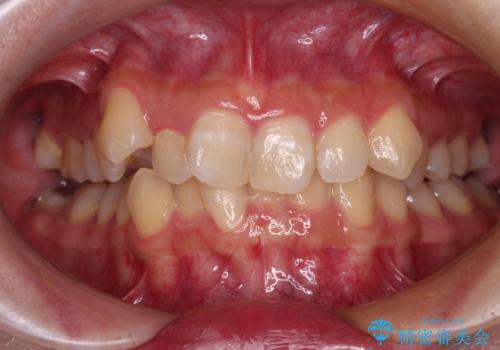

銀歯を白くしたい 一緒に矯正治療も行ない美しい口腔内に